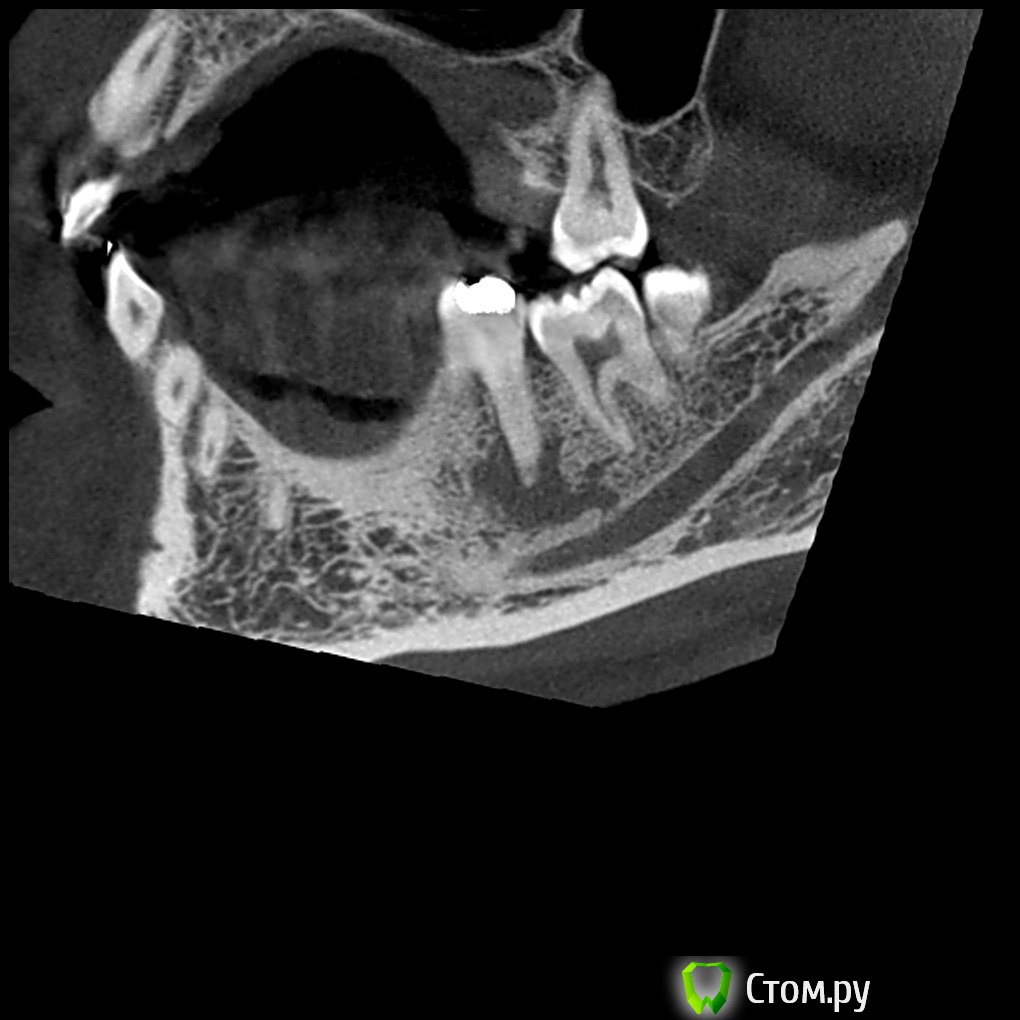

turlih) Опубликовано 29 декабря, 2013 Автор Поделиться Опубликовано 29 декабря, 2013 В 37 оператора смутила эта картина: И ретроградное пломбирование тоже рассматривают как вариант, но без УЗ насадок, микрозеркал и увеличения. В 3.7 выводить массу за апекс не собирались, эндо с резекцией верхушки медиального корня 3.7 Ссылка на комментарий

Yurij.k Опубликовано 29 декабря, 2013 Поделиться Опубликовано 29 декабря, 2013 В 37 оператора смутила эта картина:11.jpg И ретроградное пломбирование тоже рассматривают как вариант, но без УЗ насадок, микрозеркал и увеличения. В 3.7 выводить массу за апекс не собирались, эндо с резекцией верхушки медиального корня 3.7 Резекция без ретроградного пломбирования - напрасно истраченное время.Зачем 3.7 калечить ? Здесь без хирургии можно обойтись! Нужно качественное эндо. Лечение 3.6. 1 Ссылка на комментарий

Kolchanov Опубликовано 29 декабря, 2013 Поделиться Опубликовано 29 декабря, 2013 эндо с резекцией верхушки медиального корня 3.7 Ваш коллега реально на столько крут, чтобы отчекрыжить верхушку корня у нижней семерки? Нет ли аксиальной нарезки этой области. Просто поглазеть на то, какую работу по кости ему придется сделать Ссылка на комментарий

turlih) Опубликовано 29 декабря, 2013 Автор Поделиться Опубликовано 29 декабря, 2013 Ваш коллега реально на столько крут, чтобы отчекрыжить верхушку корня у нижней семерки? Нет ли аксиальной нарезки этой области. Просто поглазеть на то, какую работу по кости ему придется сделать 1 Ссылка на комментарий